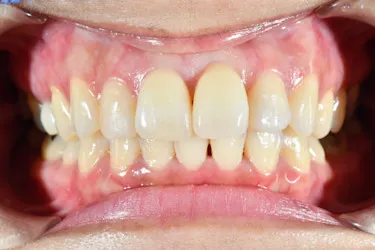

ホワイトニングも同時並行で行い、「毎週自分の歯並びの写真を撮っていたので、綺麗になっていくのが楽しみだった」という矯正体験について45歳主婦のN.T.様にお話を伺いました。

毎週自分で歯並びの写真を撮っていたので日々綺麗になっていく歯並びを見るのが嬉しく、家族からも綺麗になったねと言われました! マウスピース矯正と並行してホワイトニングも行っていたので、歯が格段に綺麗になるのを実感できたのが嬉しかったです。